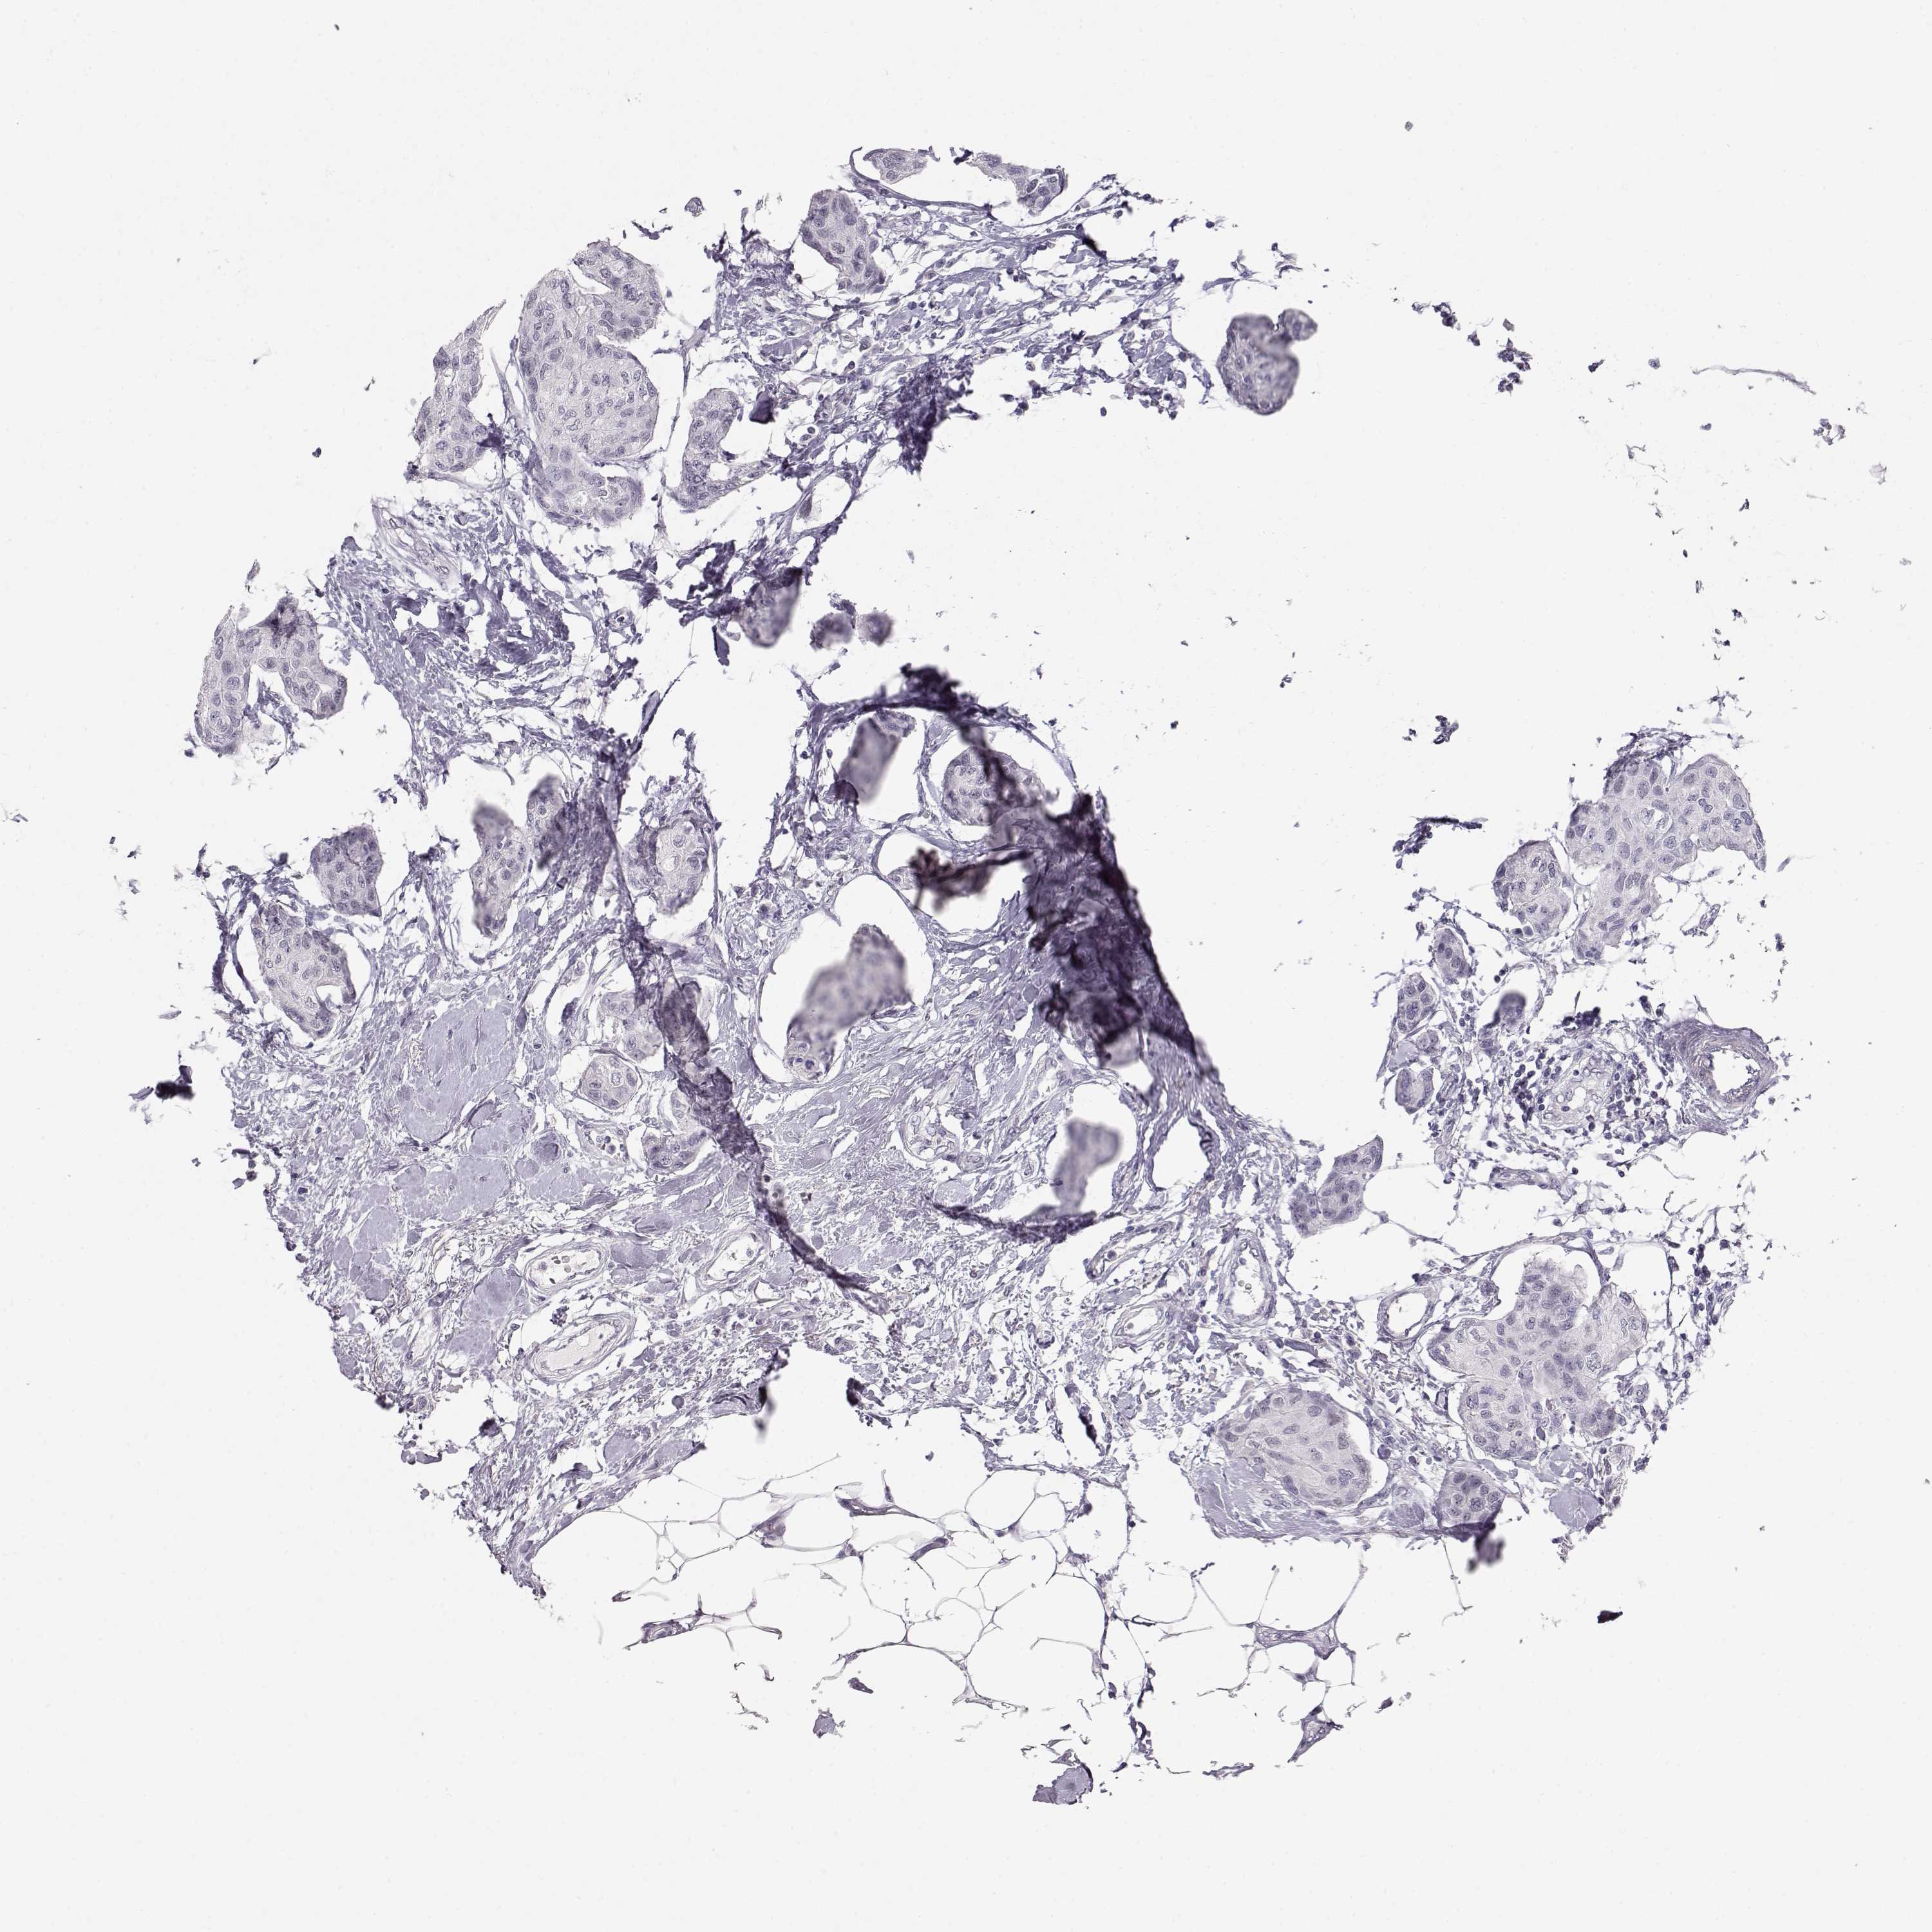

CANCER BREAST CANCER Show tissue menu

Breast cancer

Human cancer